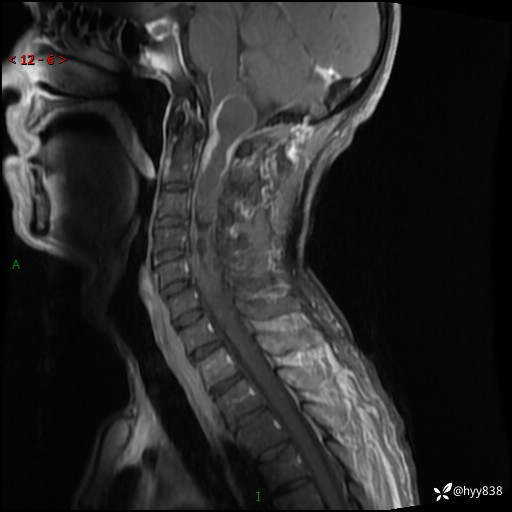

颈椎MRI平扫(sag T1WI+T2WI-fs+axi T2WI)

CE

简要病史:患者约于2年前无明显诱因出现右手麻木伴有精细活动差,无行走不稳,家属将患者送至当地县人民医院行颈椎MR提示:颈髓占位性病变。患者未系统治疗治疗。后病情逐渐加重,4个月前出现四肢无力,右侧为甚,行走不稳,伴有四肢感觉减退,伴有大便偶有失禁,现患者及家属为求进一步治疗入我院,遂以“椎管占位”收住我科。 发病以来,患者精神饮食睡眠好,大小便正常,体力体重未见明显改变。

辅助检查:MRI

临床诊断:椎管占位